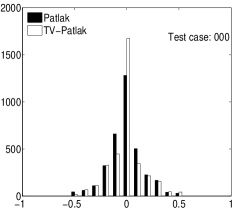

In the images shown in the figures we illustrate the calculated uptake rates of the FDG. Images for the CMRGlc can be obtained by directly scaling . In figure 1 we compare the result of using Patlak and TV-Patlak for estimating the uptake rates with respect to no noise, noise in the input function, Poisson noise in the sinogram, and finally with respect to the case in which the irreversibility assumption is violated but without noise in the sinogram or input data. In each case the histogram of the relative errors is given on the left, the Patlak image in the middle and the TV-Patlak on the right. The different scales in the histograms are due to the total number of results illustrated. When there is no noise (triples and ) the histogram illustrates results over all voxels but only one simulation, while for the noisy simulations the results are for all voxels over all realizations of the noise. The TV-Patlak images are more homogeneous in all cases and the relative errors are smaller. The figures clearly show the improvements of employing the TV-Patlak method as compared to using Patlak independently for each voxel. This is confirmed in figure 2 in which images with noise in the sinogram, positive and different noise levels in the input function are shown.